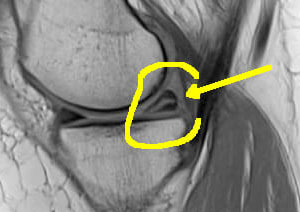

Le ménisque s'use avec le temps : il prend un aspect dégénératif sur l'irm sous la forme d'une fissure oblique blanche (ici surlignée en jaune) dans l'épaisseur du triangle méniscal.

Ces lésions dégénératives sont à priori indolores et anciennes. L'aspect de la surface méniscale est normale en arthroscopie et l'ablation d'une telle "lésion" est sans effet sur les douleurs du patient (par contre très dommageable pour le cartilage...)

La découverte de cette lésion est habituelle par une IRM chez un(e) patient(e) autour de 50 ans, mais cette lésion bénigne peut être observée plus tôt dans la vie (25-30 ans).